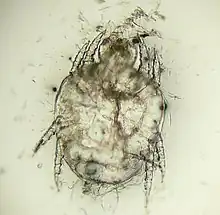

| Cheyletiella yasguri (?) from a dog | |

The adult mites are about 0.385 millimeters long, have eight legs with combs instead of claws, and have palpi that end in prominent hooks.[5] They do not burrow into the skin, but live in the keratin level. Their entire 21-day life cycle is on one host. They cannot survive off the host for more than 10 days.[6]